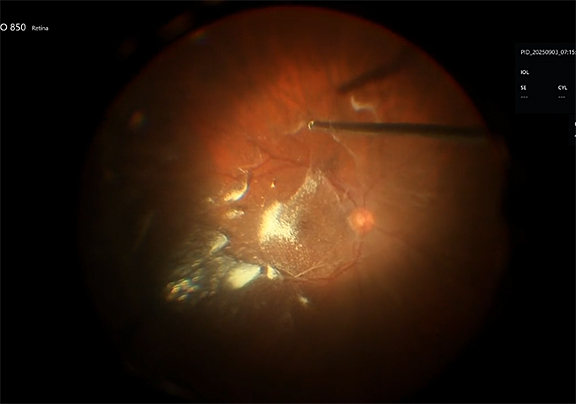

The reason why I like this technique is because it allows us to work with the intraocular foreign body in a closed system, so I don't have leakage from a large sclerotomy. I can adjust the size of the loop according to what I'm going to grab and this actually acts as an instrument. I can physically manipulate the foreign body in position. Now my fellow is depressing, and here I am nudging around it. My fellow is going to pull on the strings for me, and now I’ve grasped it. One of the keys is, as you’re pulling up on the string, that the surgeon has to advance the metal cannula toward the foreign body. Otherwise, it'll just kind of fall off, so you have to advance the instrument toward the foreign body as your assistant pulls up on the 2 strings. And then, this is where you open the eye. I could have diathermized to make this look prettier for the video, but I was just interested in getting it out. So there, we’re done. That’s all there is to it.